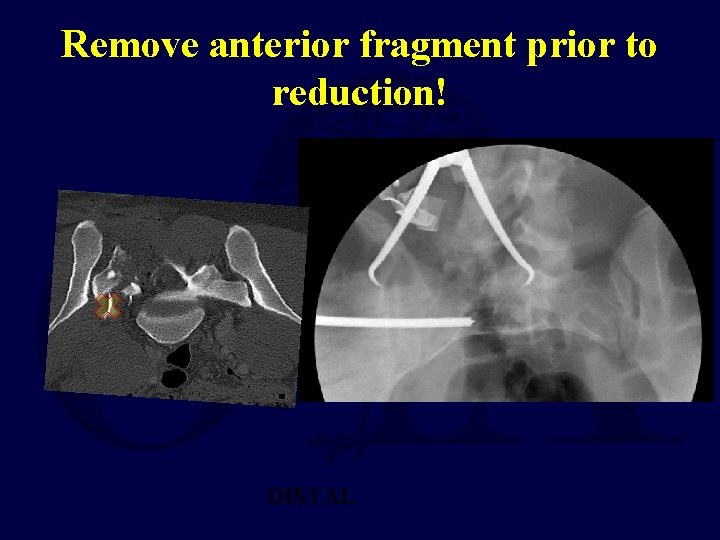

Remove anterior fragment prior to reduction! DISTAL